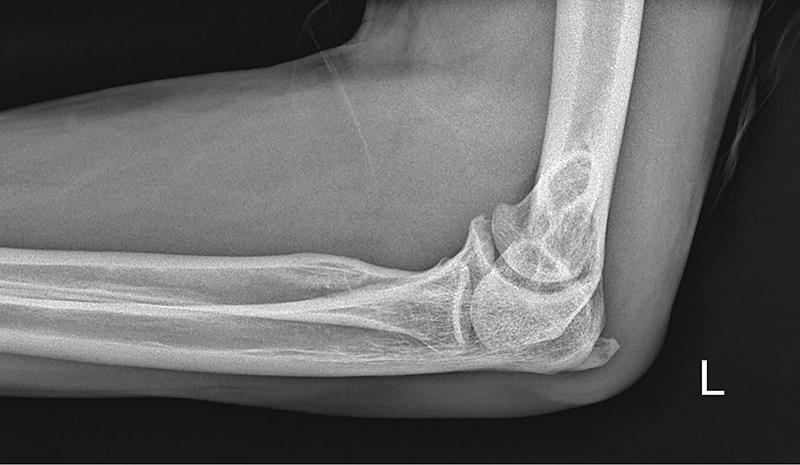

A deep learning artificial intelligence (AI) model demonstrates good area under the receiver operating characteristic curve (AUROC) and higher sensitivity in the binomial classification of paediatric elbow radiographs when compared to emergency department (ED) physicians, reports a Singapore study.

The test set revealed an accuracy of 80.4 percent (95 percent confidence interval [CI], 71.8‒87.3) for the AI model, with an AUROC of 0.872 (95 percent CI, 0.831‒0.947). [Singapore Med J 2025;66:208-214]

When compared with the physician group, the AI model demonstrated a sensitivity of 79.0 percent (95 percent CI, 68.4‒89.5 vs 64.9 percent, 95 percent CI, 52.5‒77.3; p=0.088) and a specificity of 81.8 percent (95 percent CI, 71.6‒92.0 vs 87.3 percent, 95 percent CI, 78.5‒96.1; p=0.439).

The current study included a total of 1,314 paediatric elbow lateral radiographs (patient mean age 8.2 years), retrospectively reviewed and classified based on annotation as normal or abnormal (with pathology). These images were then randomly partitioned to a development set (n=993), first and second tuning sets (validation; n=109 and 100, respectively), and a test set (n=112).

The investigators trained an AI model on the development set using the EfficientNet B1 network architecture. They compared its performance on the test set with that of five physicians (inter-rater agreement: fair). Finally, the McNemar test was used to assess the performance of the AI model and the group of physicians.